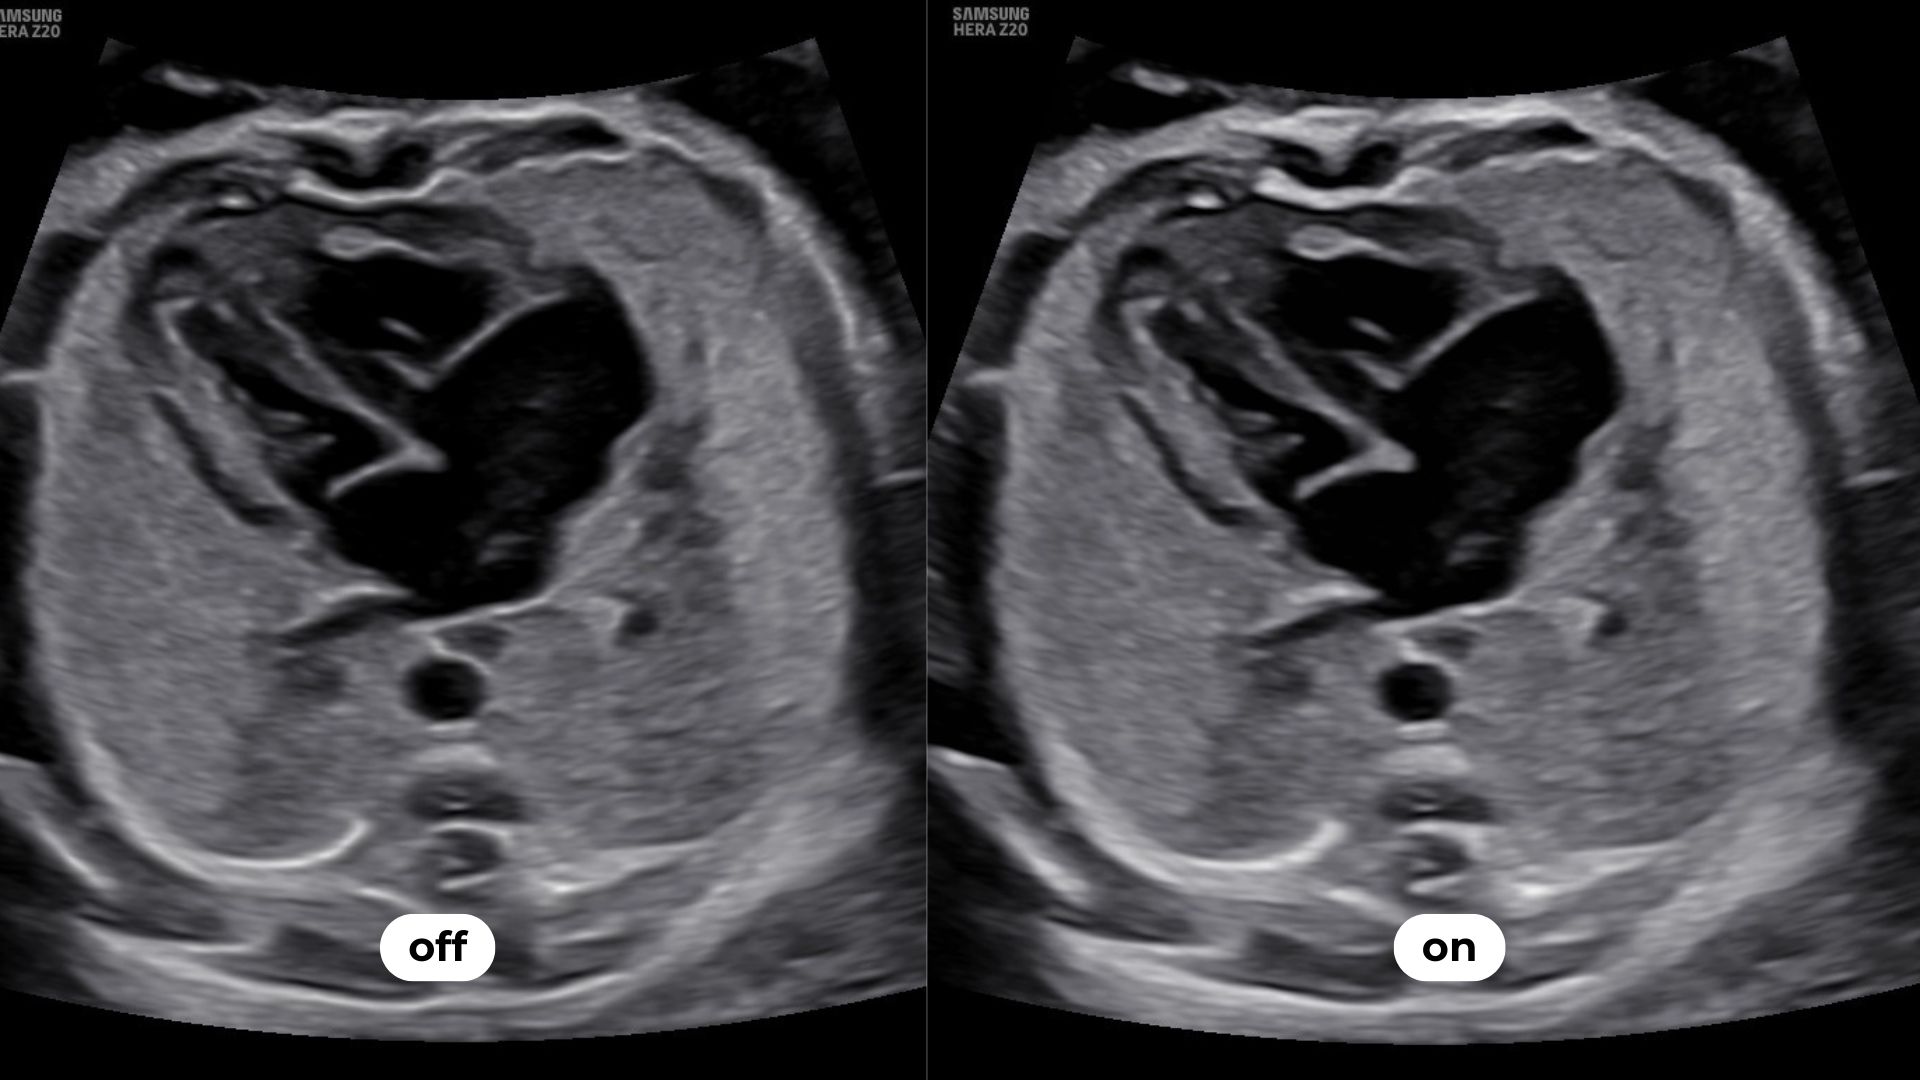

Luminant™ est un algorithme de différenciation structurelle qui transforme les contours d’une image 2D et améliore l’analyse des structures, comme pour le cœur ou le cerveau fœtal.

permet une sommation d’images réalisées sur des bandes de fréquences différentes et limite les surexpositions et atténuations du signal. Cet outil met en évidence des zones habituellement masquées comme les contours de la boîte crânienne.